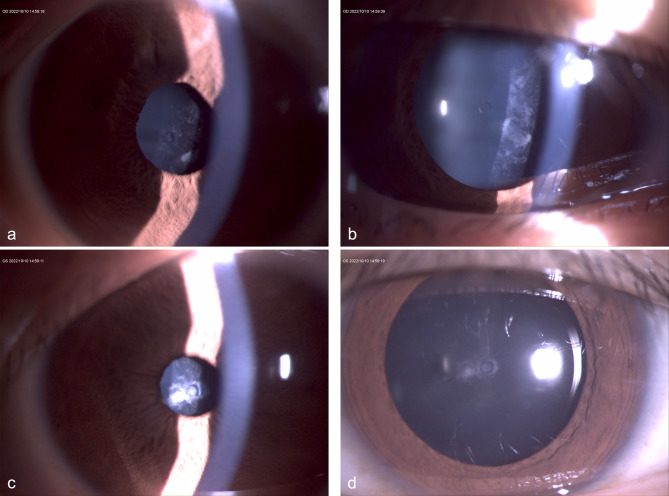

Case presentation: A 19-year-old woman with high myopia underwent bilateral TICL implantation. Preoperative imaging revealed shallow anterior chambers, high crystalline lens rise, small pupils in Pentacam HR (Oculus, Germany), and short ciliary processes in ultrasound biomicroscopy (UBM). Both eyes developed low postoperative vaults. Nineteen months later, she returned with bilateral 0 μm vault and anterior subcapsular cataracts. Repeat UBM confirmed short ciliary processes and partial footplate slippage beneath the ciliary sulcus. The left TICL was replaced with a larger lens, but 0 μm vault recurred. The right eye was monitored without further intervention.